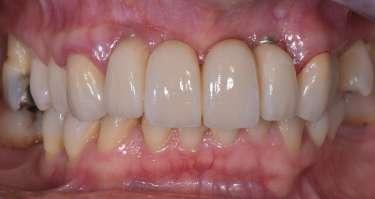

Fig. 1 – Cavità su 1.5 Fig. 2 – Particolare della cavità del dente 1.5 Fig. 3 – Preparazione Laser Er:YAG Pluser con lunghezza d’onda di 2940 nm di LAMBDA DoctorSmile, Italia. Fig. 4 – Particolare della cavità dopo gengivectomia Fig. 5 – Particolare della cavità completata dopo la preparazione della dentina Fig. 6 – Restauro finale in composito (Asteria Tokuyama, Japan)